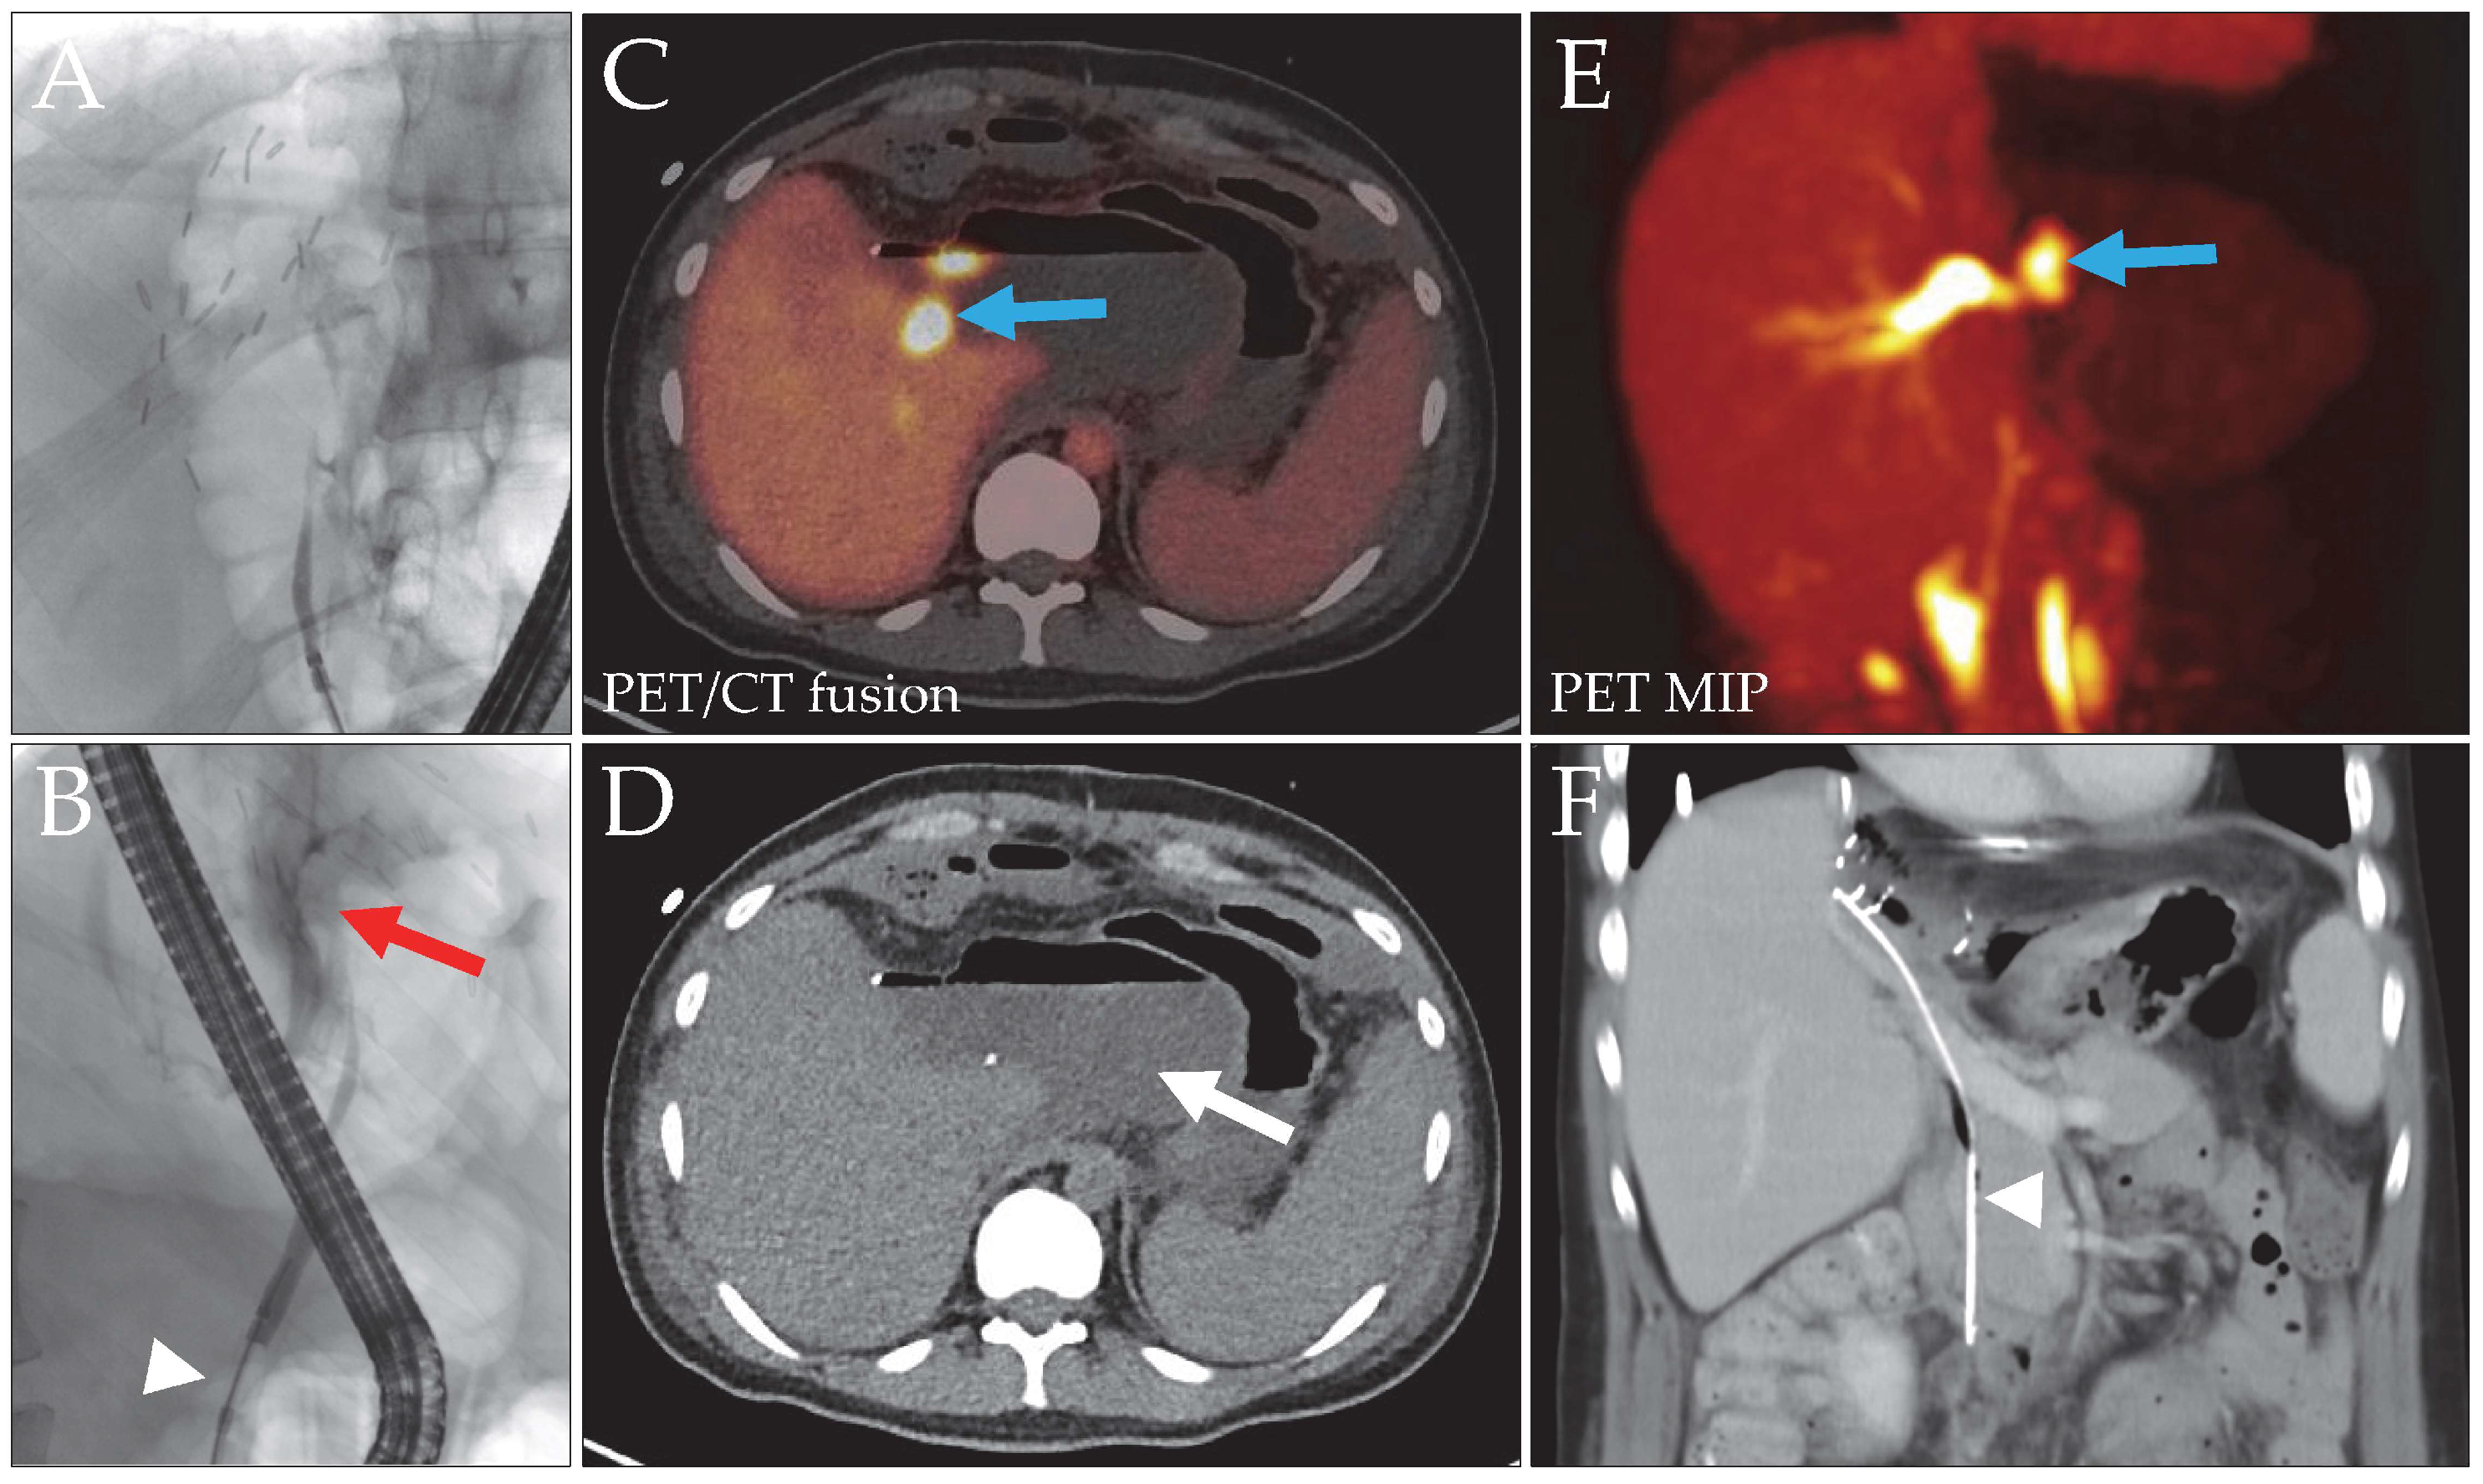

Figure 2. Patient 3, liver donor, with a bile leak after left hemihepatectomy for LDLT. The initial ERC image (A) did not show the biliary tree. With a blocked catheter ((B), white arrowhead), a contrast media extravasation (red arrow) without clear leak localization was evident. Intervention with stent placement was not possible due to the stricture. DAZA-PET (C,E) revealed a central bile leak (blue arrows, SUVmax 43.0/SUVmax/mean liver tissue 9.4/7.0), draining into a large bilioma ((D), arrow). The space-occupying bilioma caused external compression of the central bile ducts, resulting in distention of the right intralobar ducts. After bilioma and leak repair surgery, a long stent was implanted to facilitate bile outflow ((F), arrowhead). MIP, maximum intensity projection.